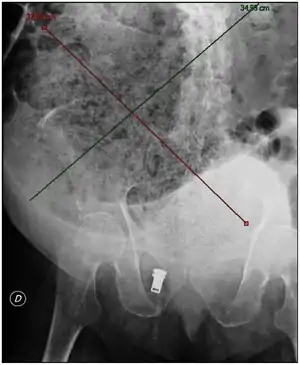

تشخیص سفتشدگی مدفوع با وجود شرح حال یبوست یا بیاختیاری سرریزی، یافتههای معاینه شکم و معاینه راستروده با انگشت، و پرتونگاری شکم مسجل میشود.